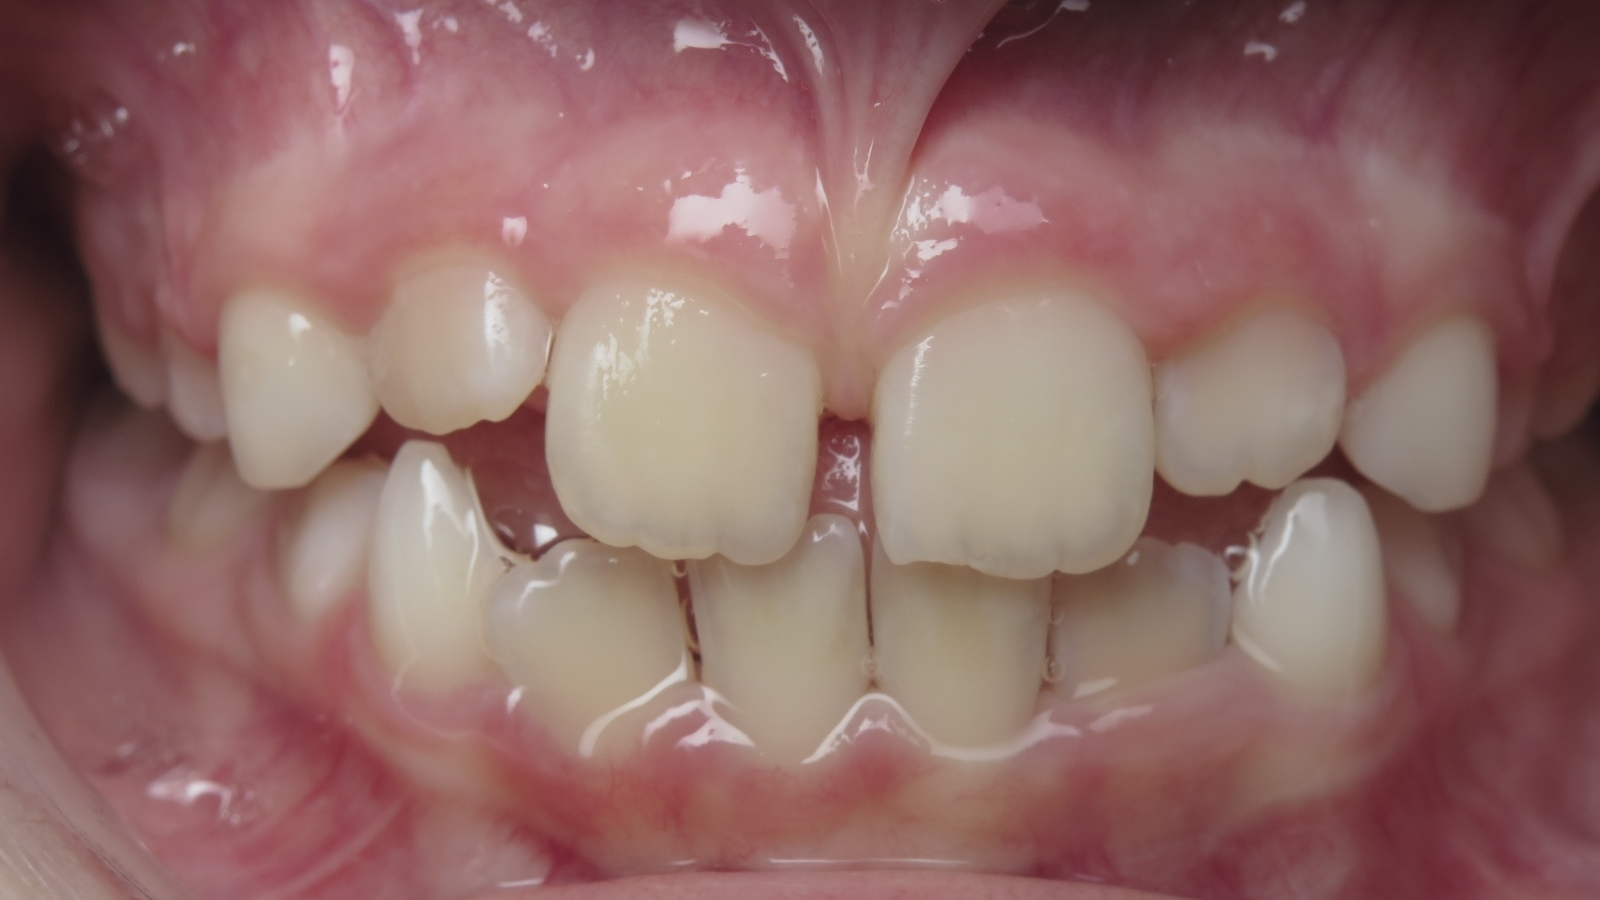

18 béance inversé droit 4 ans

inversion des dents postérieur et espace entre l'arcade du haut et du bas (béance)

bilan de début et en cours de traitement